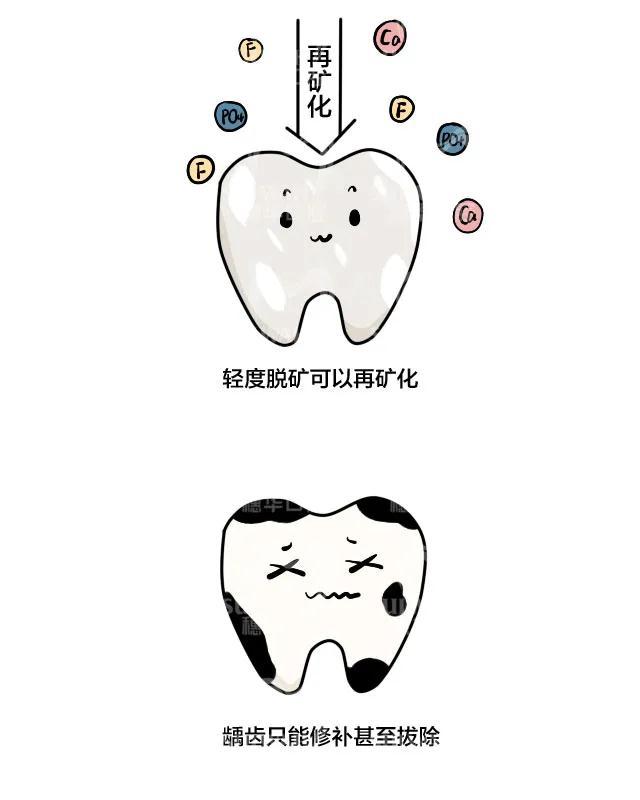

牙釉质脱矿可以说是龋齿的前兆,最显着的特征就是牙齿表面粗糙,色泽

蛀 牙 实 例 健康的牙齿 牙釉质开始脱矿 龋齿的初始状态